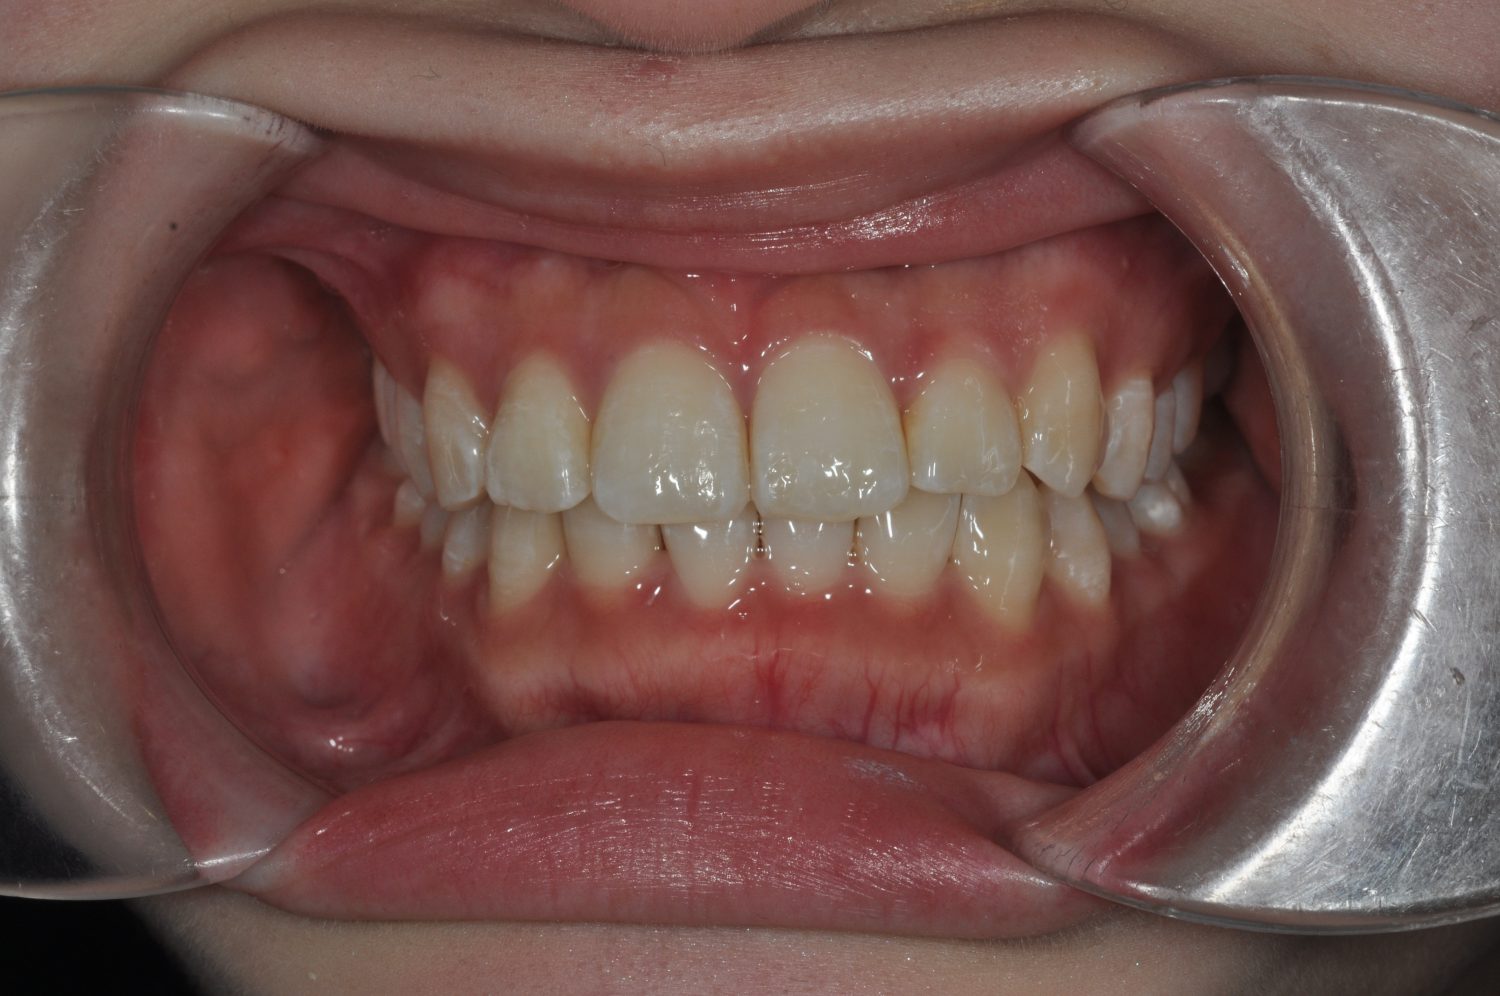

| 主訴 | 前歯部の叢生と正中の不一致 |

| 治療内容 | 軽度の叢生の改善を行うために、非抜歯でのマルチブラケット装置による治療を行った。 |

| 想定されたリスク | 矯正後に後戻りする可能性がありました。 |

Ⅰ期治療で叢生、反対咬合の改善をセクショナルアーチとMPAを使用して改善した後、成長観察を行っていました。永久歯の萌出したため、Ⅱ期治療を開始することとなった。上下顎とも骨格的に問題がなかったため、非抜歯で治療を行った。